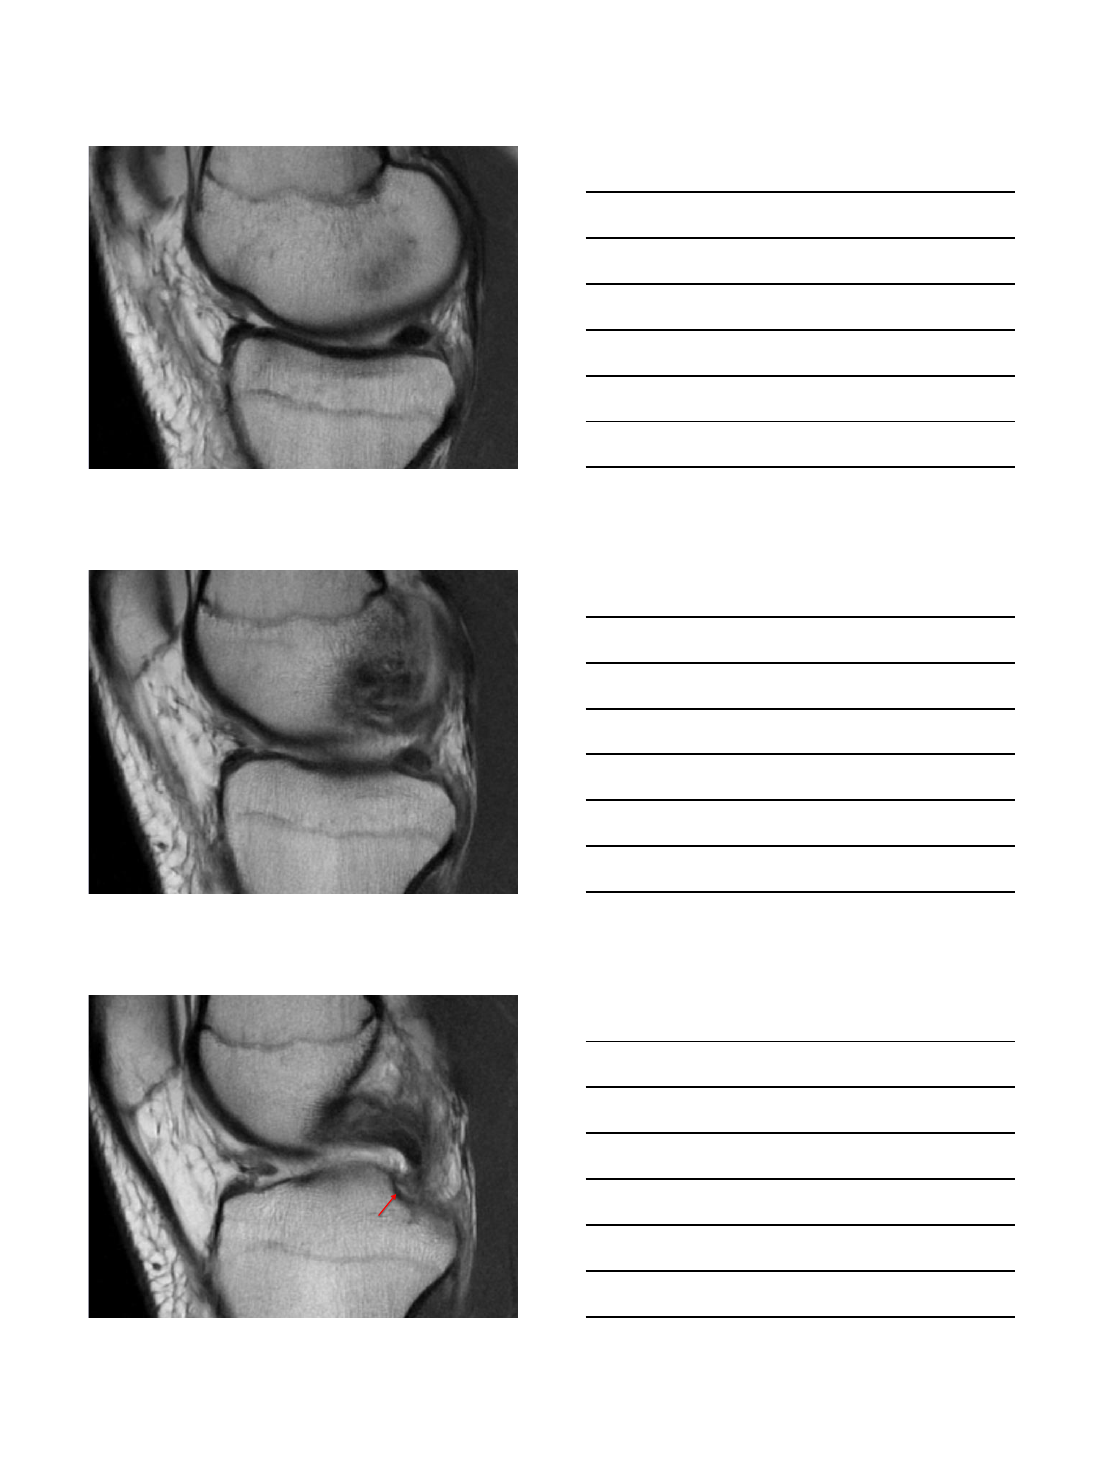

Radial Tear at Tibial Root

47 year-old female with medial knee pain. Prior

history of meniscal root re-attachment.

Radial tear

• Radial split at the post horn root junction MM. “Ghost sign”

•Subacute subchondral medial plateau fracture with mild bone plate

depression and focal area of devitalized bone

One year later